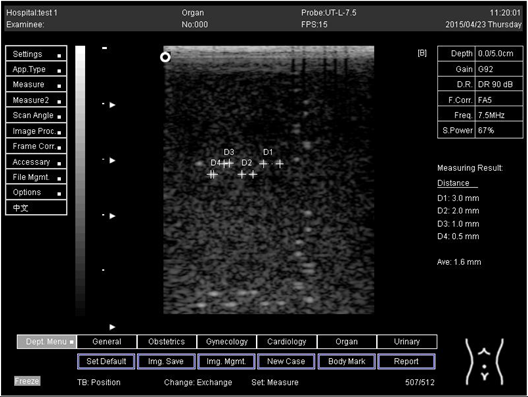

5.0 Lateral resolution

Biomimetics 07 00130 i012

D1 = 3.0

D2 = 2.0

D3 = 1.0

D4 = 0.5

Regarding phantom 2, only linear probes were applied. This is because phantom 2 is shorter than phantom 1, and the linear probe had a lower penetration setting compared to the curve probe. Therefore, a linear probe is more suitable for the phantom. Based on the results recorded on phantom 2, axial and lateral resolution measurements were still under an acceptable value since the percentage difference between the actual distances was less than 2% (Table 6).